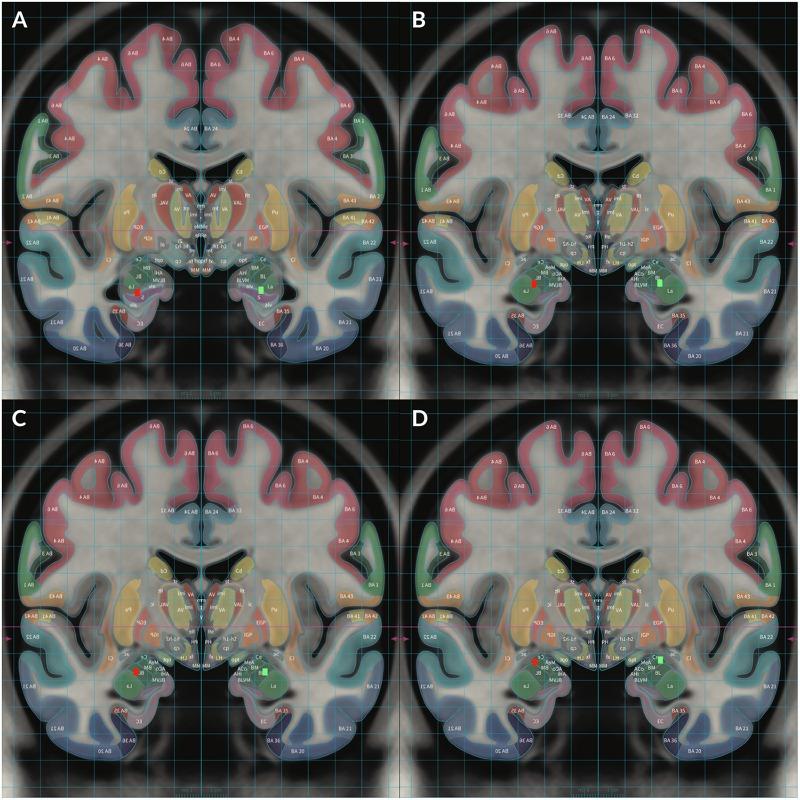

Accurate localization of complex human experiences such as emotions, dreaming, creativity, and consciousness to specific cerebral structures or neural networks has remained elusive despite technological advances. We report the use of acute deep brain stimulation (DBS) to evoke behavioral and emotional effects by applying electrical stimulation (ES) at various voltage strengths to the basolateral and central subnuclei of the amygdala in addition to the head of hippocampus (HC) for two subjects with medically refractory post-traumatic stress disorder (PTSD). Our results suggest that the amygdala could be a node in a neural network responsible for the generation of complex vivid mental imagery and integrated sensory experiences similar to John Hughlings Jackson's "dreamy state" and "double consciousness," which have been classically associated with temporal lobe epilepsy during uncinate seizures. That we were able to elicit similar vivid, dynamic, complex, bizarre, and original mental imagery with ES in non-epileptic subjects suggests that Jackson's seizure related "dreamy state" and "double consciousness" may arise from heightened innate brain mechanisms with the amygdala acting as a node in the neural network responsible for physiologic dreaming and creative functions. Furthermore, our subjects experienced different emotions with different stimulation strengths at various electrode contacts. Our results suggest that higher voltage stimulation of the amygdala and HC at 4-5 V leads to predominantly negative responses and 2-4 V stimulation showed inversely coupled positive and negative responses of the amygdala in either hemisphere which may imply hemispheric dominance of emotional valences without relation to handedness. Due to the unique and complex responses dependent on location and strength of stimulation, we advise that all patients receiving DBS of the amygdala undergo acute stimulation mapping in a monitored setting before selecting therapeutic parameters for chronic stimulation.

尽管技术不断进步,但将诸如情绪、梦境、创造力和意识等复杂的人类体验精确地定位到特定的脑结构或神经网络仍然难以实现。我们报告了对两名患有难治性创伤后应激障碍(PTSD)的受试者使用急性深部脑刺激(DBS),通过在不同电压强度下对杏仁核的基底外侧和中央亚核以及海马头部(HC)施加电刺激(ES)来诱发行为和情绪效应。我们的结果表明,杏仁核可能是神经网络中的一个节点,负责产生复杂生动的心理意象和综合的感官体验,类似于约翰·胡克林·杰克逊的“梦幻状态”和“双重意识”,这些在经典上与钩回发作期间的颞叶癫痫有关。我们能够在非癫痫受试者中通过电刺激诱发类似的生动、动态、复杂、奇异和原始的心理意象,这表明杰克逊与癫痫发作相关的“梦幻状态”和“双重意识”可能源于大脑先天机制的增强,杏仁核作为神经网络中的一个节点,负责生理梦境和创造性功能。此外,我们的受试者在不同电极触点处以不同刺激强度体验到了不同的情绪。我们的结果表明,在4 - 5伏对杏仁核和海马进行较高电压刺激主要导致负面反应,而2 - 4伏刺激显示杏仁核在任一半球的正负反应呈反向耦合,这可能意味着情绪效价的半球优势与利手无关。由于存在依赖于刺激位置和强度的独特而复杂的反应,我们建议所有接受杏仁核DBS治疗的患者在选择慢性刺激的治疗参数之前,在监测环境中进行急性刺激图谱绘制。